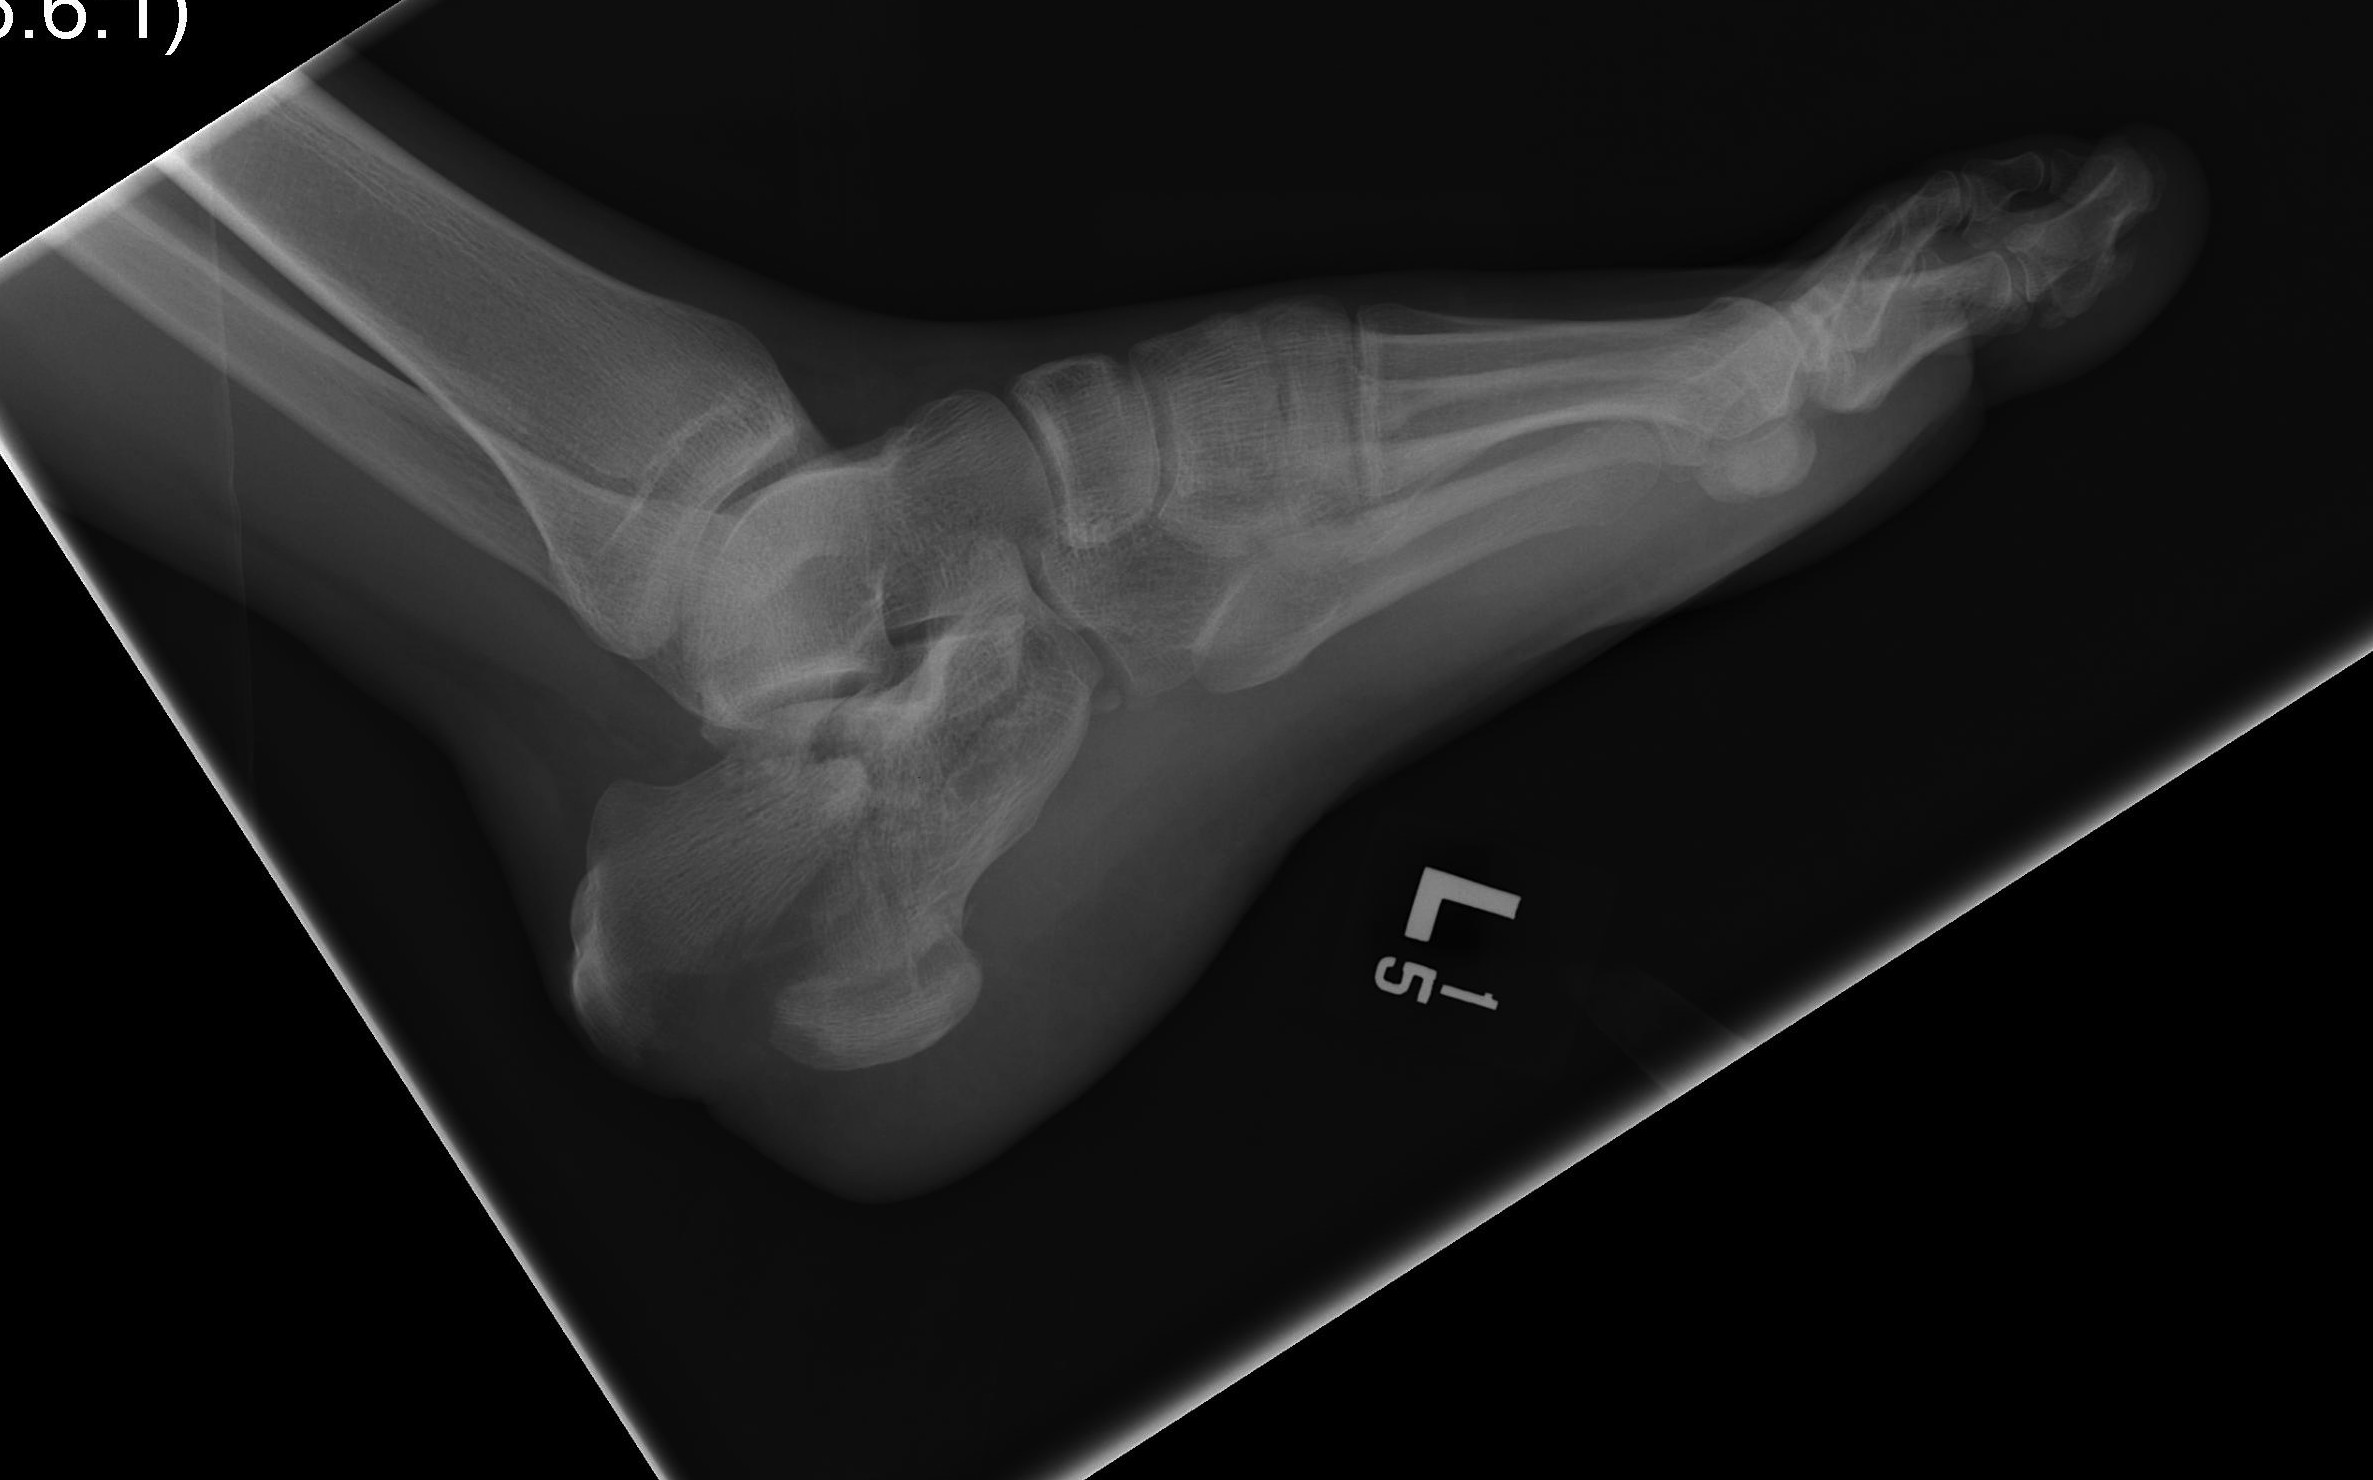

Calcaneal Malunion

Issues

Varus hindfoot - locks midfoot

Peroneal impingement

Shoewear problems

Options

Lateral wall exostectomy and peroneal tenolysis

Calcaneal osteotomy

STJ arthrodesis

Osteotomy for calcaneal malunion surgical technique PDF

Vumedi calcaneal osteotomy for malunion video

Results

Farouk et al Foot Ankle Int 2019

- 18 varus calcaneal malunions

- combined subtalar joint fusion / calcaneal osteotomy / lateral wall exostectomy

- outcome score increased from 60 to 80